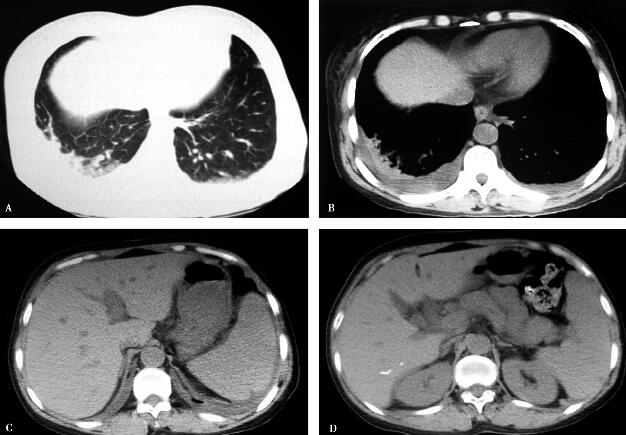

7.全腹CT:(2013年7月15日,图1)双肺下叶少许斑片影、双侧胸腔少量积液,肝右叶胆管结石,胆囊炎,脾增大,少量腹水,上腹部肠系膜周围可见少许渗出。

图1